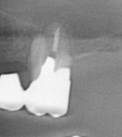

症例3

ブリッジの支えになっていた奥歯です。歯肉、骨ともに吸収が大きいです。金属で連結されているため、患者さんご自身は動揺に気づかないことがあります。ブリッジは過重負担(力負け)して歯周病の骨吸収が急激に重度となることがあります。

左の写真のレントゲン写真です。